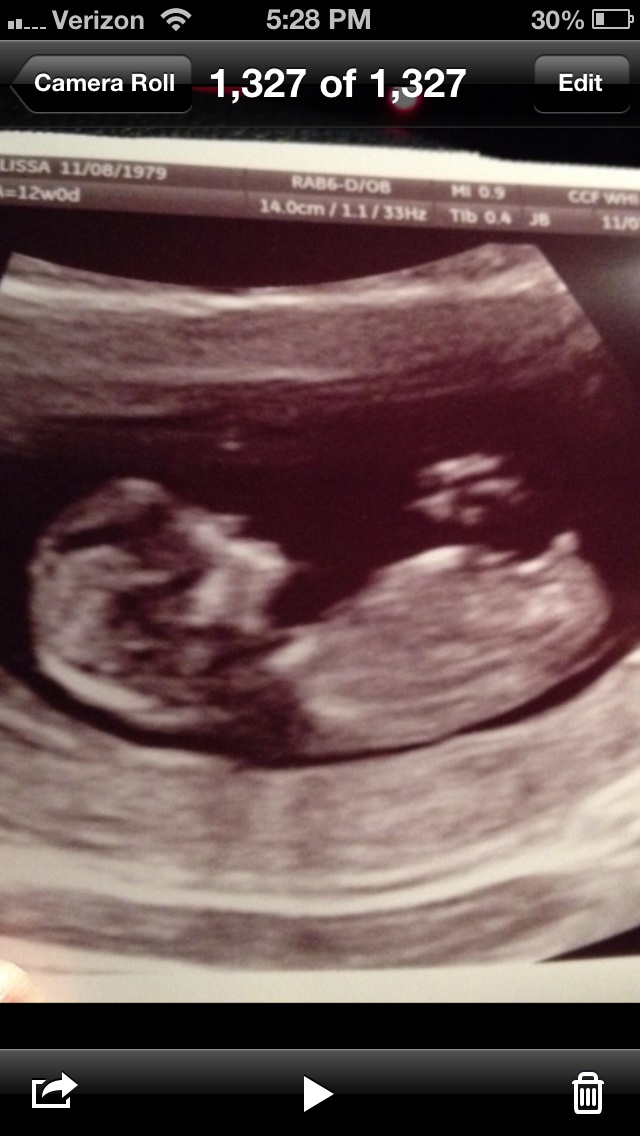

I think boy?! Is that a penis??Attachment 22024

It's not technically a penis...but well on its way to being one! Very boyish nub!

It says 12w0d on the top right. Looks boyish to me.

very boyish , and as it is at 12w it will rise. already angled up, thick end

Nice boy nub, congrats!